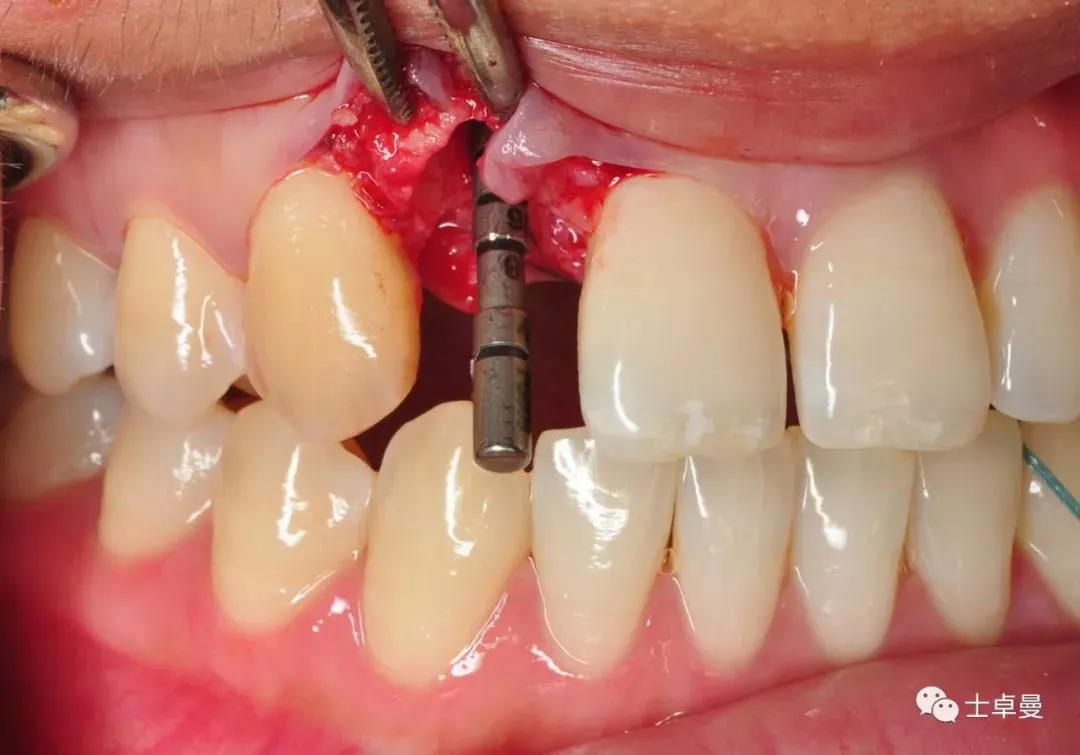

·       腭侧壁上定点,先锋钻确认种植体植入位置;

偏腭侧定点

·       放置指示杆确定种植体方向,方向无误后,逐级备洞,腭侧骨板部门攻丝,植入3.3mm×14mm士卓曼钛锆合金亲水表面骨水平锥柱状种植体 (BLT) 种植体;

方向杆显示种植体轴向位置

·       初期稳定性大于35NCM,ISQ值73;